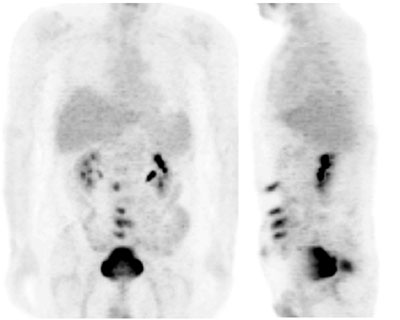

Fig. 27. - Imágenes coronal y lateral de tomografía por emisión de positrones de cuerpo completo. Varón de 52 años con antecedentes de cáncer de colon intervenido quirúrgicamente. En PET de control se aprecian varios focos de hipercaptación de la [18]FDG en línea media abdominal (coincidentes con localización de cicatriz quirúrgica). Dichos focos una vez analizados por biopsia, se confirmaron como motivados por la infección de diversos puntos de sutura en el paciente.